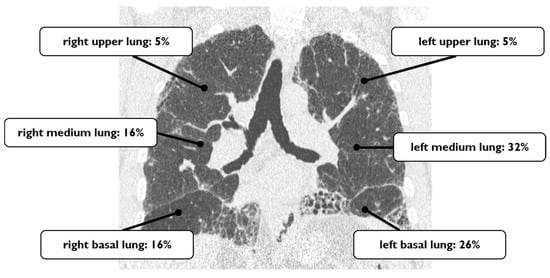

4.2. Acute Exacerbation